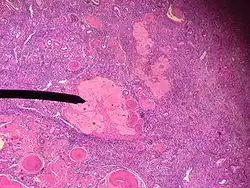

Атретическое тело человека

Атретическое тело (лат. corpus atreticum) — временная эндокринная железа в составе яичника.

• Источники развития: первичные, вторичные и третичные фолликулы.

• Строение: 1) погибший овоцит первого порядка, 2) остатки блестящей оболочки, 3) остатки фолликулярного эпителия лучистого венца, 4) гипертрофированные интерстициальные клетки (текациты).

• Функции: уничтожение мутировавших овоцитов, предупреждение многоплодия, эндокринная (андрогены, эстрогены), регуляция циклических и возрастных инволюций молочной железы.